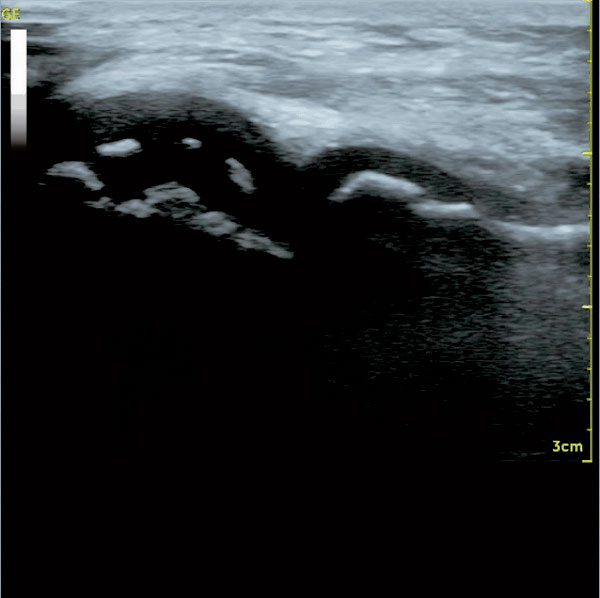

- 超音波画像診断装置

*人体に対して無侵襲な超音波で、腱・筋肉、軟部組織、関節等を検査します。損傷の範囲や程度が診断できます。

肩関節腱板完全断裂

肘関節遊離性骨軟骨障害